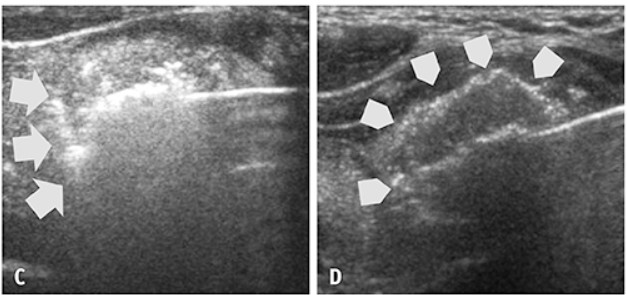

Βασικές τεχνικές του Ablation περιλαμβάνουν τις transisthmus approach (προσπέλαση δια του ισθμού του θυρεοειδούς) και moving-shot technique (τεχνική μετακινούμενης βελόνης) με στόχο τη δημιουργία ενός υπερηχογενούς τόξου (hyperechoic arc) (υπέρηχος)

υπερηχογενές τόξο (hyperechoic arc) στον Υπερηχο